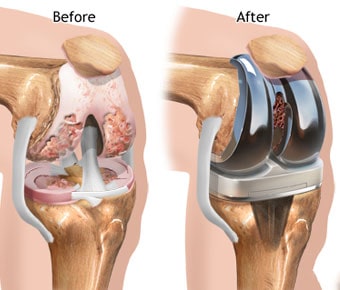

MBBS, M.Ch - Orthopaedics, MS - Orthopaedics Orthopedic surgeon,Joint Replacement Surgeon,Spine Surgeon (Ortho)

Director - Joint Replacement , Arthroscopy And Spine